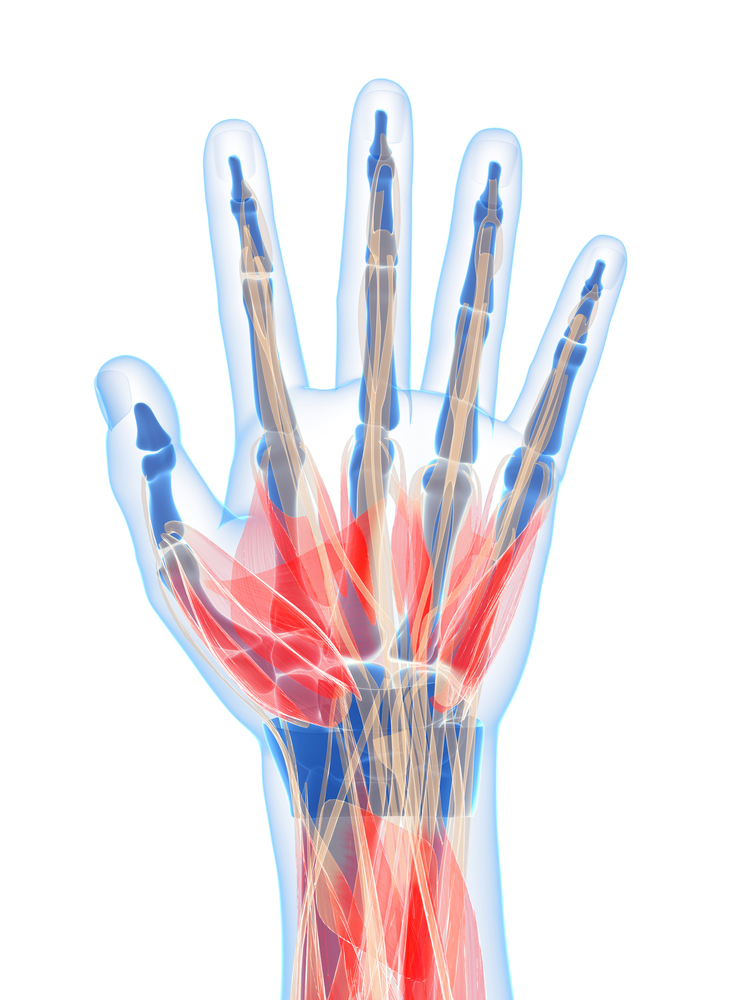

손가락 마디 통증 원인

손가락 마디가 뻣뻣하고 부딪혔을 때 찌릿하여 통증을 느끼는 경우가 있습니다. 특히 날씨가 추워지면 손가락 마디 통증이 더 심해지는 경우도 많습니다.

일반적인 통증 외에도 손가락을 움직일 때마다 소리가 나는 경우, 손가락이 두꺼워지고 변형이 생길 경우, 손가락 마디가 붓는 경우, 손가락 장시간 사용이 어려울 경우엔 손가락에 문제가 발생했다는 신호가 될 수 있으니 정확한 원인을 찾기 위해 진단을 받아보시는 게 중요합니다.